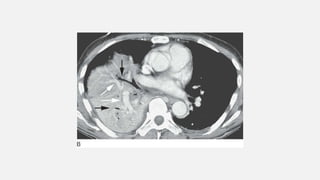

• #22 Enhanced CT in a patient with right middle and lower lobe pneumonia shows homogeneous consolidation, preserved lung volume, air bronchograms (black arrows), and opacified vessels (white arrows), appearing denser than surrounding consolidated lung (i.e., the “CT angiogram” sign).Preserved Lung Volume In the presence of consolidation, because alveolar air is replaced by something else the volume of affected lung tends to be preserved

• #24 Consolidation: patchy opacities. A: Chest radiograph in a patient with pulmonary edema due to renal failure shows patchy perihilar consolidation. B: Patchy areas of fluffy consolidation are seen on CT. The fluffy margins are due to variable involvement of alveoli at the edges of the pathologic process.